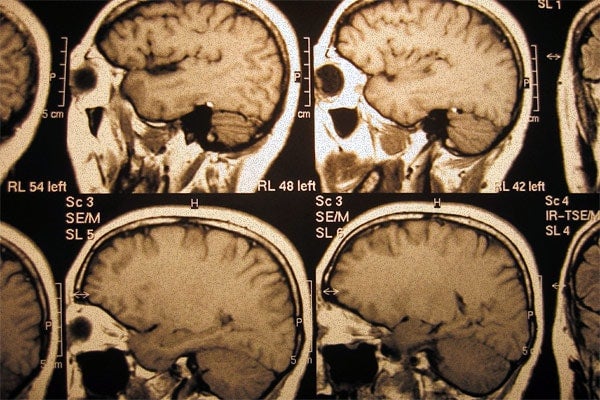

Scientists at U of T's Tanz Centre have shaped the course of neurodegenerative disease research (image by U of T News)

The need to better understand, treat and even prevent diseases such as Alzheimer’s and Parkinson’s grows increasingly urgent as Canada’s population ages. In this first instalment of a two-part series on the University of Toronto’s world renowned Tanz Centre for Research in Neurodegenerative Diseases, writer Niamh McGarry looks at how U of T scientists are leading the way.